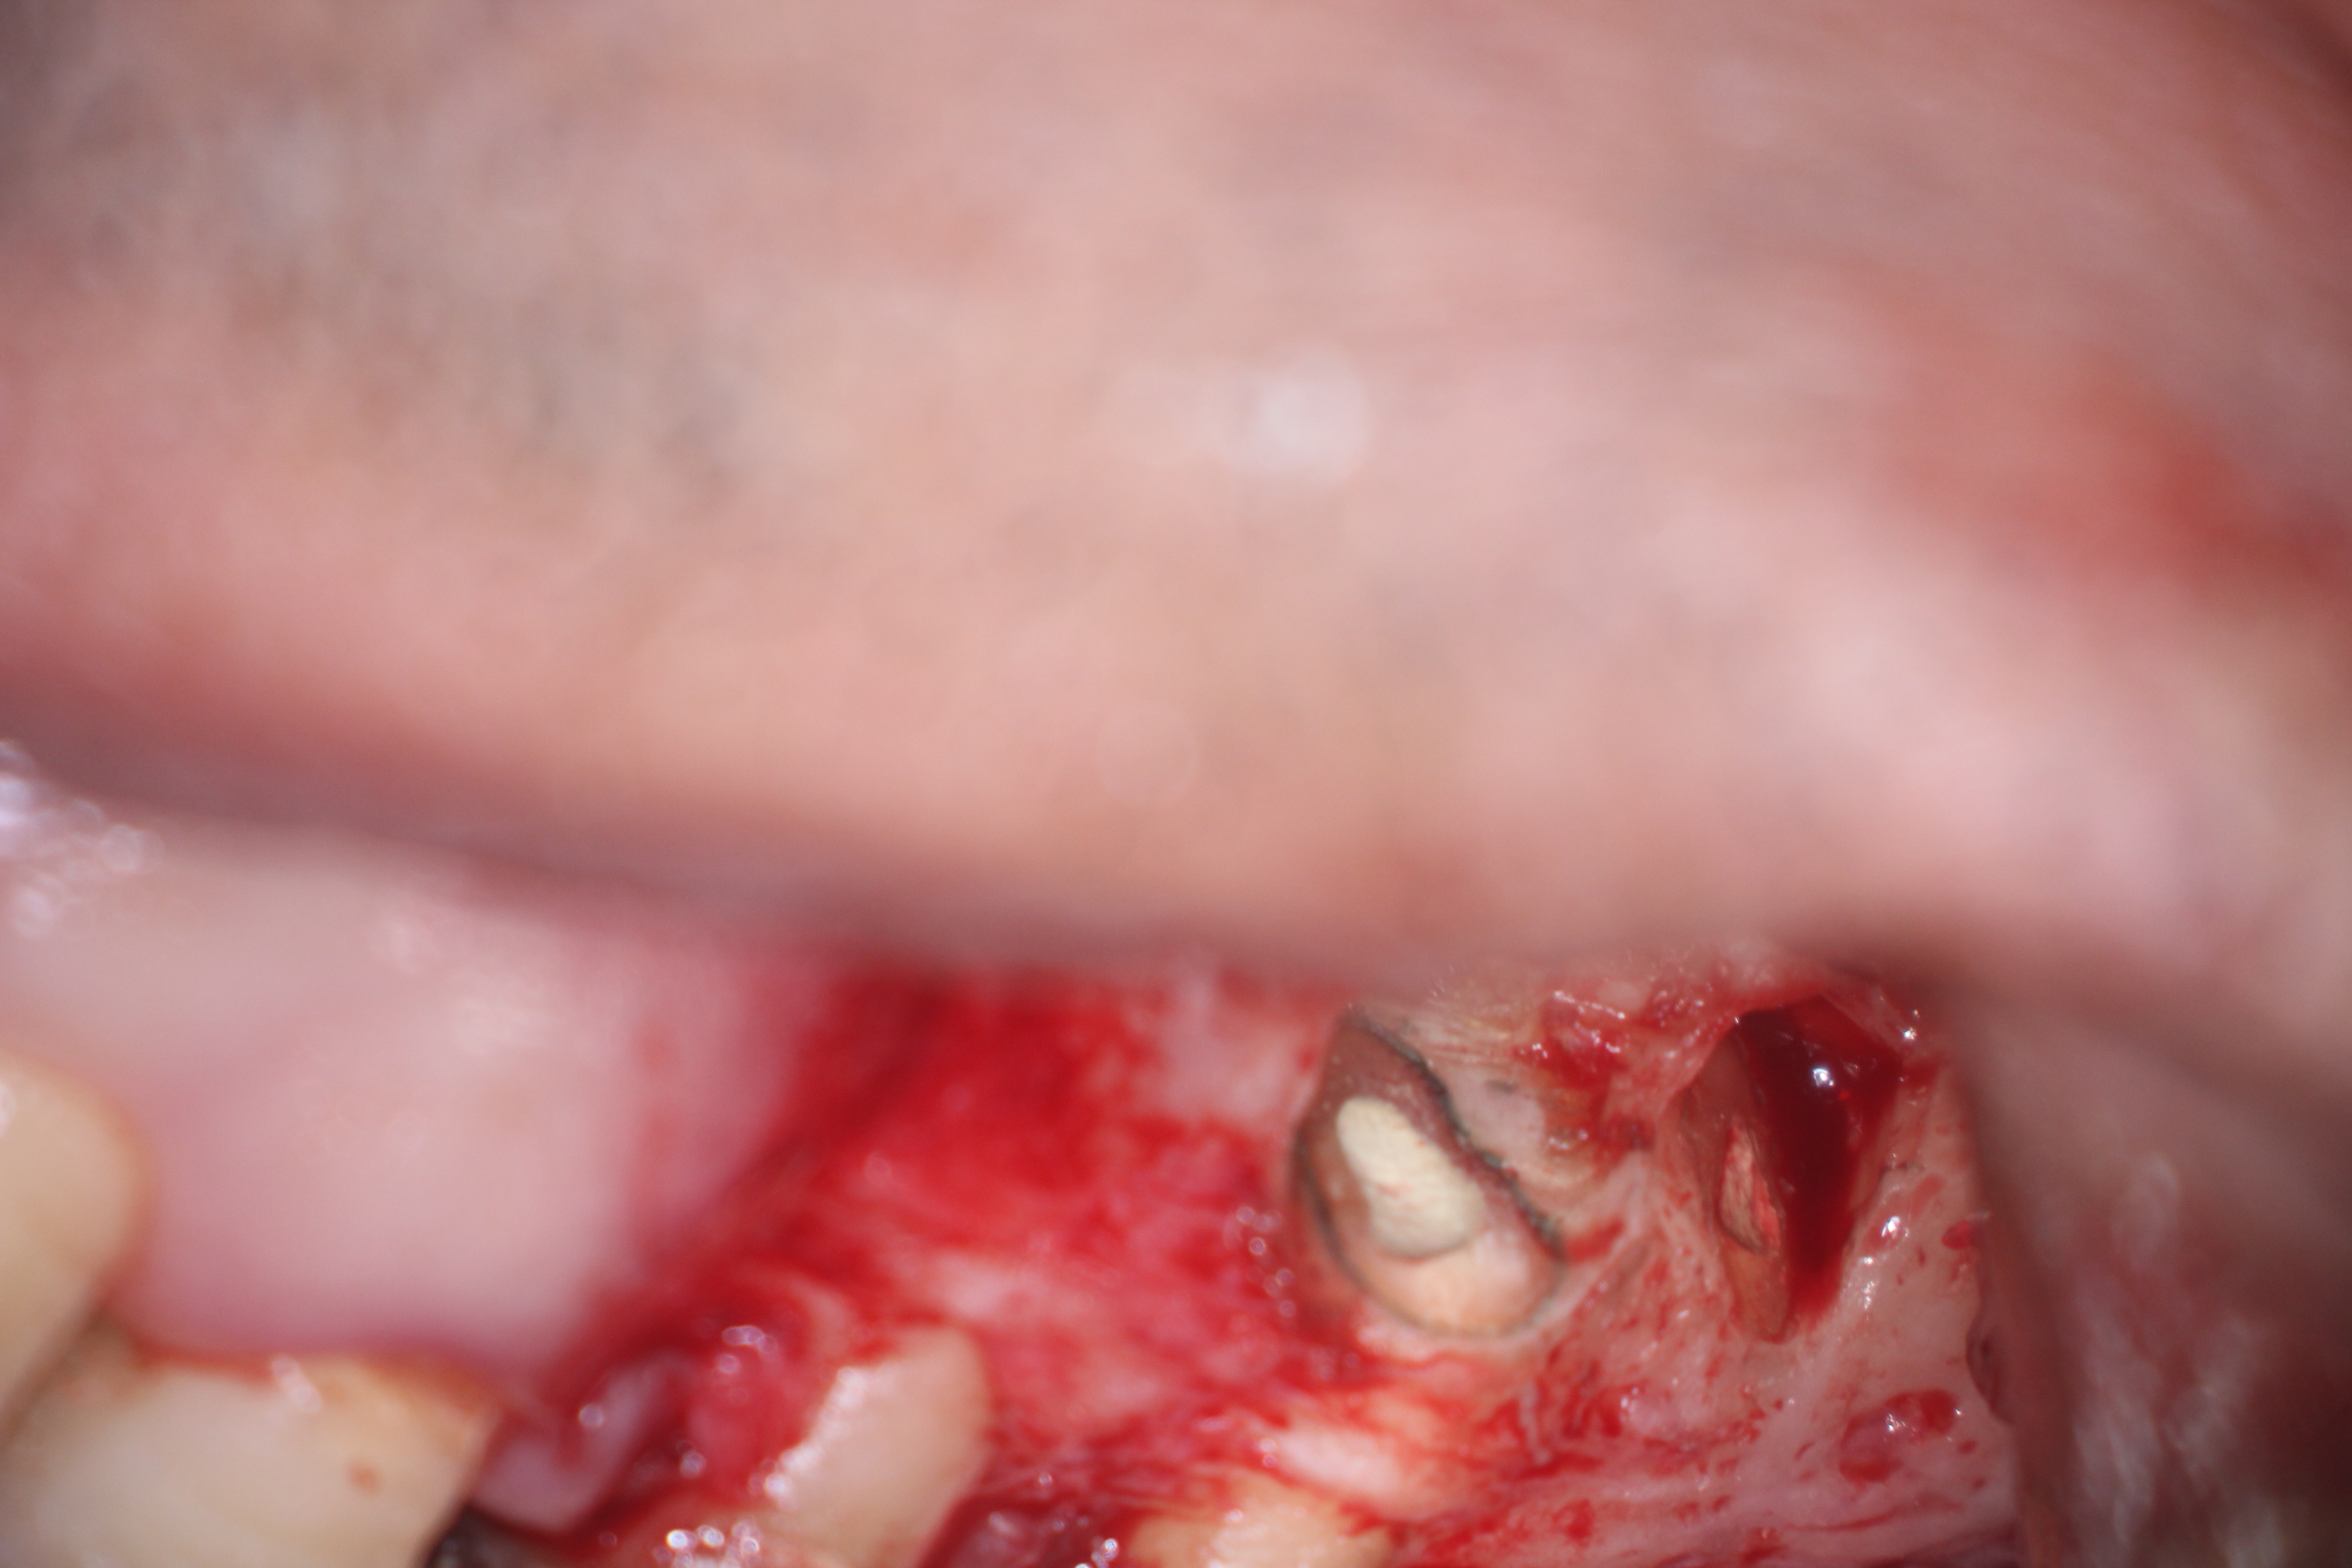

Fig 16. 3-mm root resection with methylene blue staining.

Figure 16

Clinical procedure: In the case of a root-end filling (Figure 15), once the apical 3 mm of the root has been resected (Figure 16) the canal system is then opened and cleaned with surgical ultrasonic tips to create the retro-preparation (Figure 17). After this is completed, the retro-preparation is dried and MTA is then placed and condensed in that space creating the retro-filling (Figure 18 through Figure 20).